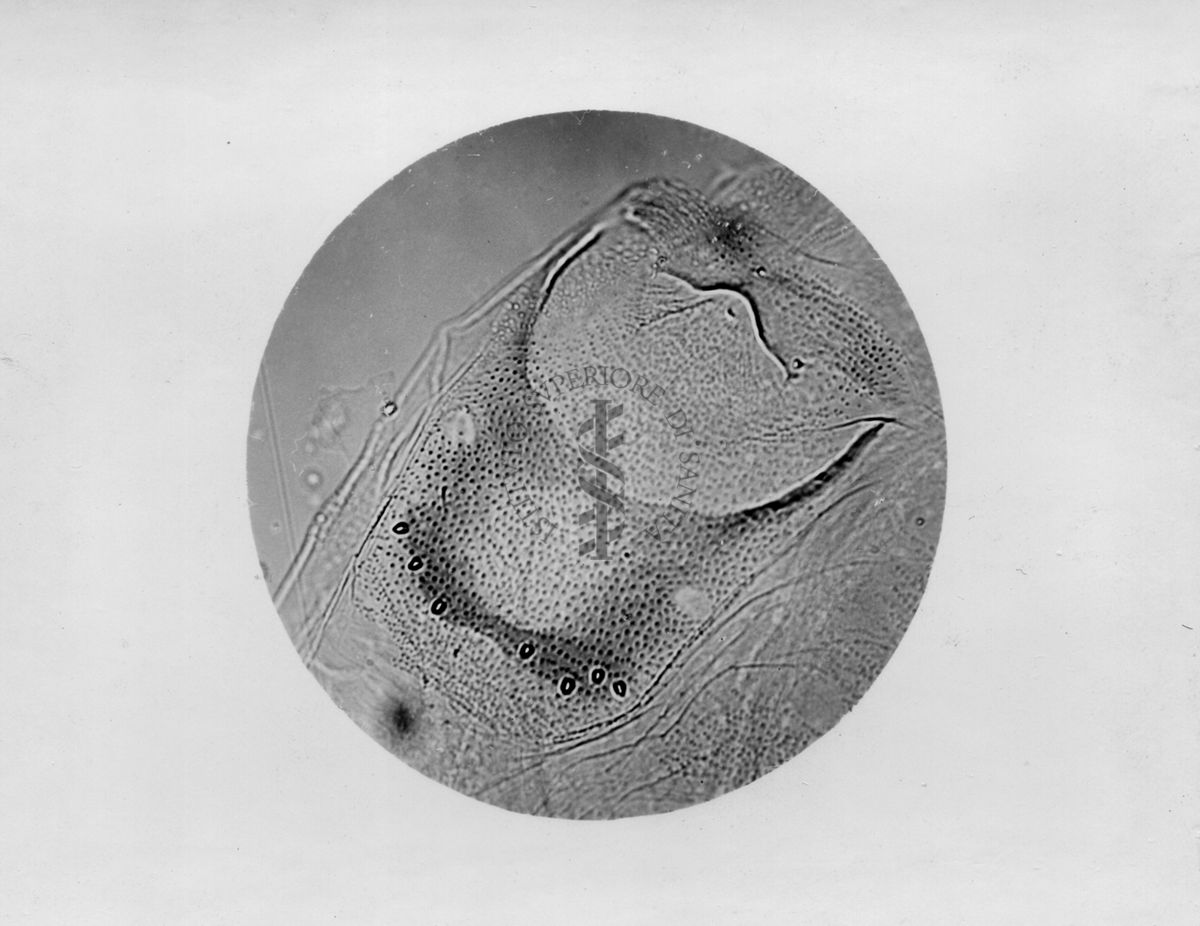

Microfotografie illustranti differenze morfologiche tra le specie P. Perniciosus e P. Perfiliewi

Microfotografia illustrante differenze morfologiche tra le specie P. Perniciosus e P. Perfiliewi